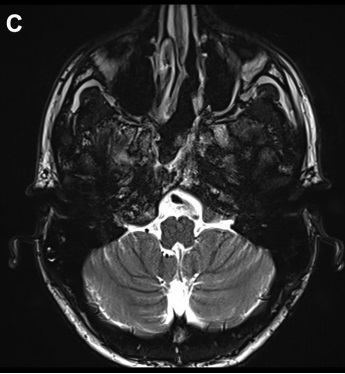

病情回顾:福教授一例复杂脊索瘤手术案例,这位病人的颅底脊索瘤较为复杂,长在了颅底斜坡、鞍旁、侵犯了海绵窦内的面部感觉及运动神经,并压迫脑干。位置及其复杂,手术风险较大,手术具挑战。患者情况危机急需手术,面对如此复杂棘手的脊索瘤,福教授会如何做手术决策?

在详细分析了肿瘤的位置及生长特性后,其主刀医生福教授为病人选择了神经内镜下经鼻手术入路可直接抵达肿瘤位置,风险较低。该病人海绵窦长在鼻腔之后距离约1cm,手术时福教授注意保护窦里的神经血管,用2小时得以暴露瘤体。颈内动脉就在这里附近,需要特别注意保护,破裂出血随时会有致命风险。

手术后较大部分的肿瘤被切除,很小部分瘤体和神经、血管、脑干等缠粘无法切除。术后病人将住院治疗8-10天。